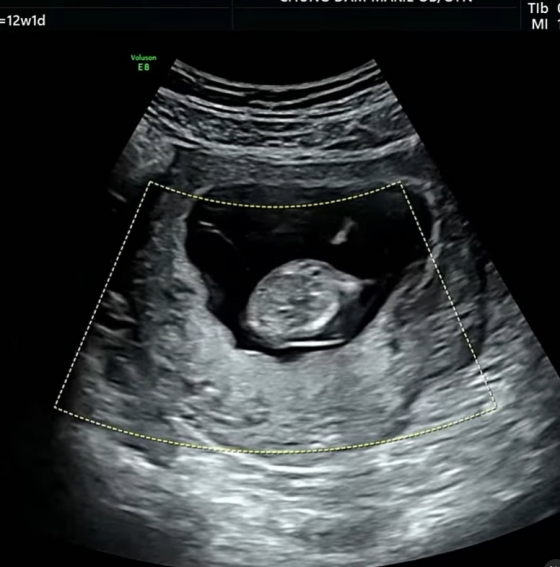

배슬기는 7일 초음파 사진과 함께 "ㅋㅋㅋㅋㅋㅋ 너무 아들임"이라고 밝혔다.

앞서 배슬기는 "올봄은 원 없이 꽃놀이했다. 마지막은 신난 우리 리슬이 12주차 초음파. 날 닮았나 아주 흥이 많아 가만히를 안 있네"라고 밝히며 초음파 영상에서 아기가 이리저리 움직이는 모습을 담기도 했다.